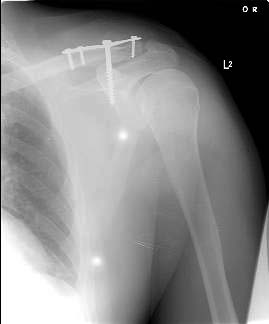

Since we have no experience with external fixation of the clavicle, we did not use this method. However, it is very interesting to see. We elected to use a T plate with a screw into the coracoid as shown in the X-ray below.

AM>We elected to use a T plate with a screw. Any comments would be appreciated.